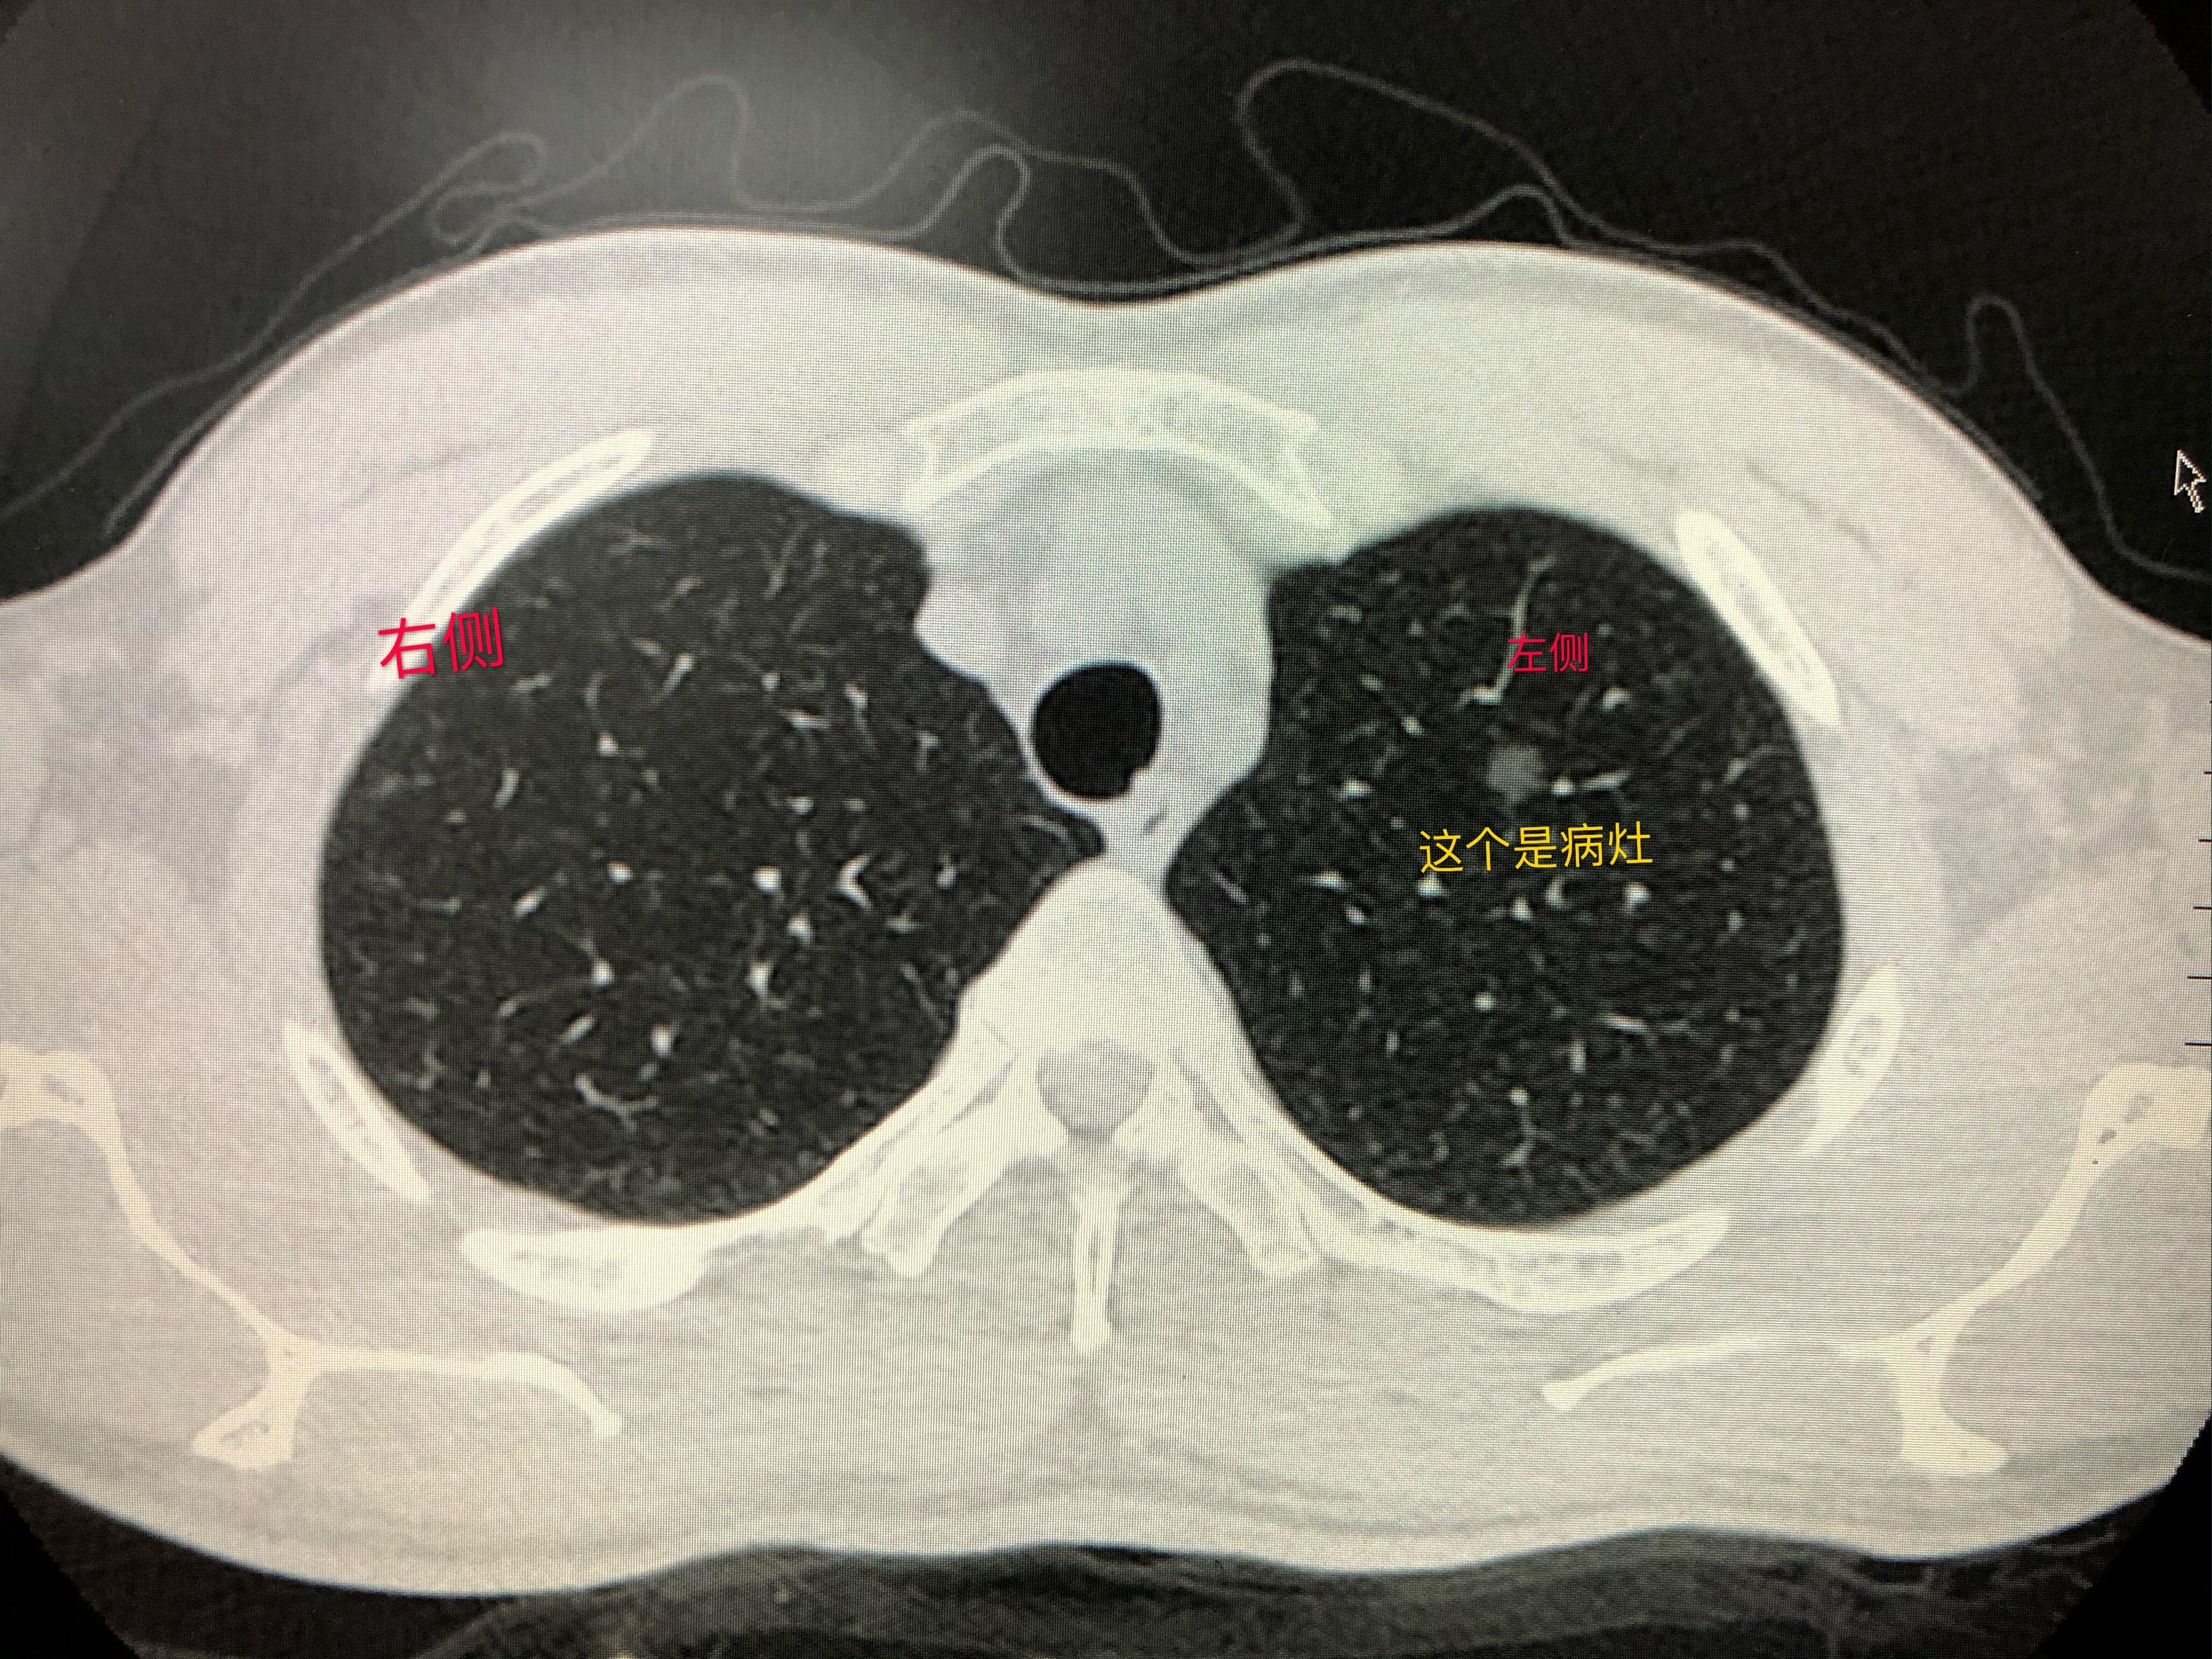

肺磨玻璃结节典型病例分享 患者需要上传什么样的照片 - 好大夫在线

左下肺磨玻璃结节.jpeg